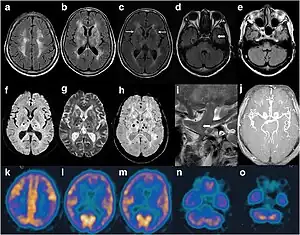

Cranial imaging of an FFI patient. In the MRI, there are abnormal signals in the bilateral frontoparietal subcortical area. MRA showed smaller distal branches of cerebral arteries. | |